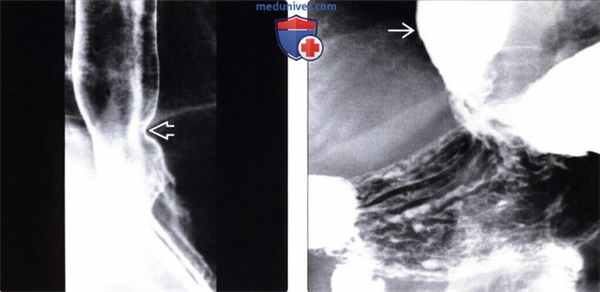

Рис. 2. Картина «стеклянного пищевода» (густая контрастная взвесь плохо проходит по пищеводу и задерживается на его стенках, создавая вид стеклянного сосуда). Стрелками обозначены стенки пищевода. Терминальный отдел пищевода сужен за счет стеноза

Рис. 3. Манометрия пищевода. Давление в нижнем пищеводном сфинктере очень низкое (а), сокращения пищевода визуализируются только в верхней части пищевода (б), амплитуда сокращений в теле пищевода резко снижена, начиная с середины (в)